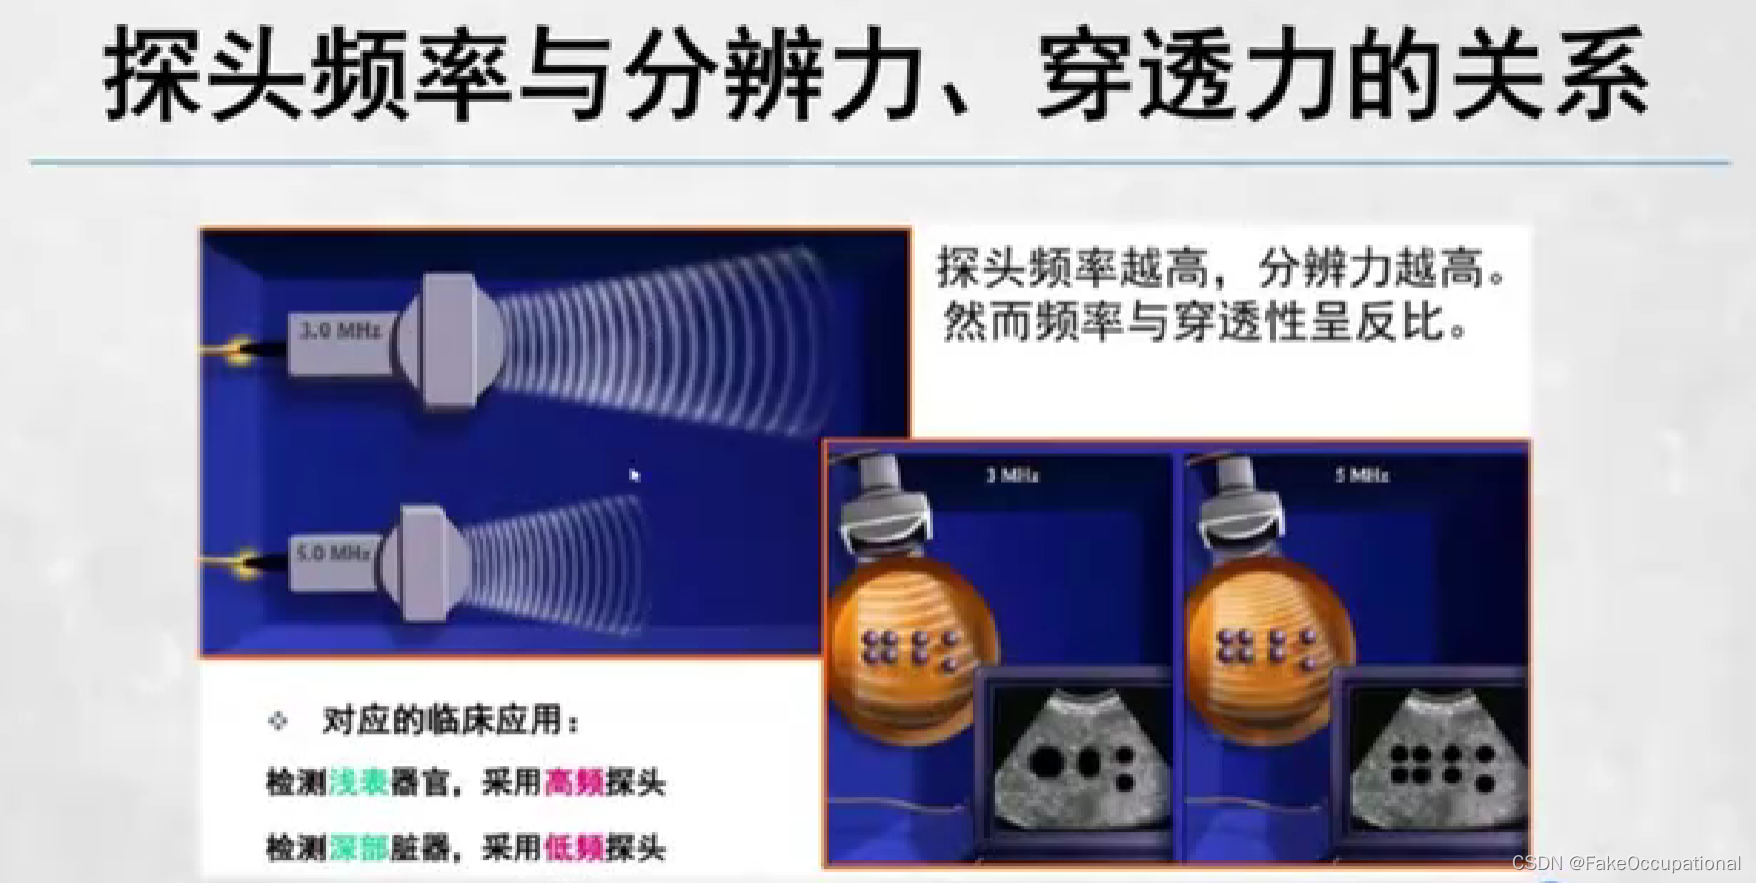

3、仪器:对仪器没有特殊要求,探头频率以2.5-5.0MHZ.

凸阵或扇形超声探头,成人选用频率3.5MHZ儿童选用频率5.0MHz

- 仪器选择常用电子相控阵探头

- 成人2.5-4.0MHz新生儿和儿童5.0-7.0MHZ